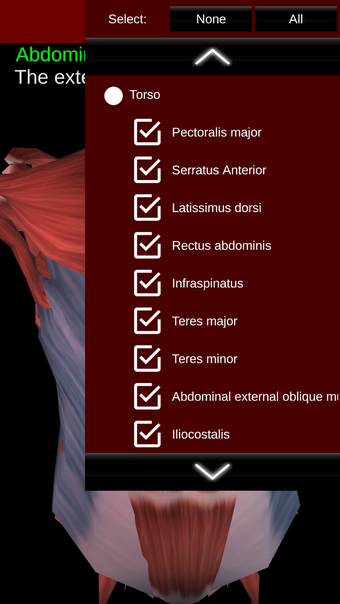

Esta herramienta educativa proporciona una descripción de cada músculo del cuerpo humano, así como un modelo tridimensional del sistema muscular. Con sólo tocar con el dedo, la aplicación revelará la información pertinente.

Los usuarios pueden hacer zoom sobre el músculo, así como elegir si ocultar o mostrar los datos. La orientación puede ser horizontal o vertical, según convenga más.